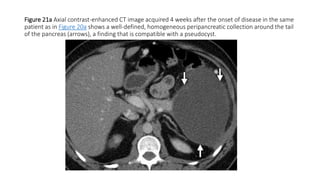

Figure 21a Axial contrast-enhanced CT image acquired 4 weeks after the onset of disease in the same

patient as in Figure 20a shows a well-defined, homogeneous peripancreatic collection around the tail

of the pancreas (arrows), a finding that is compatible with a pseudocyst.